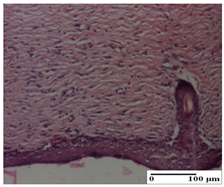

At day 21, for groups that were treated with the tested ointments, dermal collagenization for the PPo and APPo groups was observed in all three types of skin lesions, which was also noticed for APo group in incision and excision. For the AP group, significant dermal collagenization was found for incision and thermal burn. For excision, in addition to this collagenization, the presence of discrete dermal edema was also observed. For the APo group, dermal collagenization was observed in the excision but with highlighting of the hair follicle and atrophy of the sebaceous glands (Table 6).

We found superior results on days 6 and 9, both in terms of wound contraction and re-epithelialization, with the best results being obtained with the ointment that assumed the synergistic effect of apitherapy–phytotherapy–natural polymers principles. These effects are supported, in addition, by the histological results, where, from the ninth day, for the treated groups, dermal collagenization is observed, sometimes important (AP group) or dermal collagenization with rare inflammatory elements. On day 21, dermal collagenization and restoration of histological structure occurred for all treated groups, and healing occurred without keloid scars.